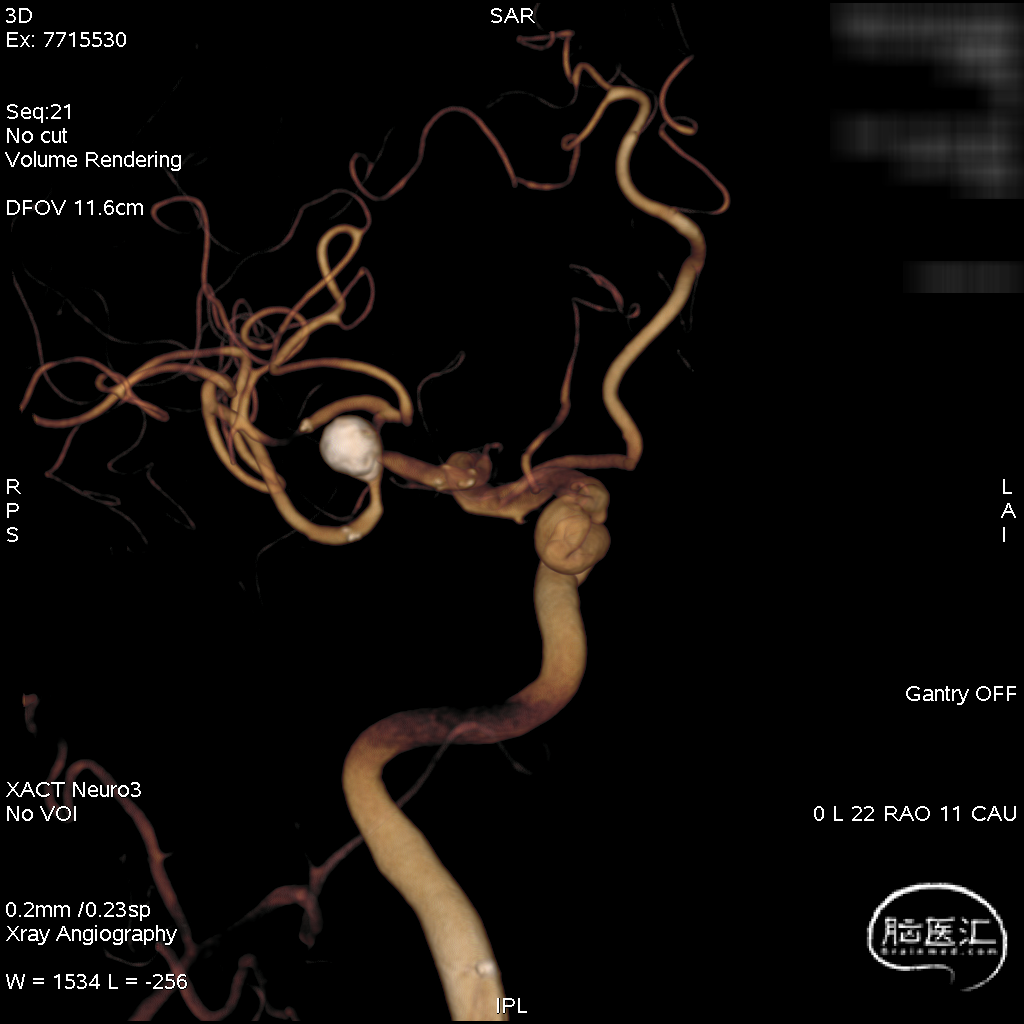

三维重建:显示左侧MCA分叉部未破裂动脉瘤,约8.2mm*8.6mmm,瘤颈3.8mm,顶端有子瘤。

术前工作位与三维重建:显示右侧MCA分叉部未破裂动脉瘤,6.9mm*7.2mm,瘤颈7.4mm。该病例之困难在于M1迂曲成袢。

术后三维重建,支架贴壁良好,动脉瘤完全栓塞。